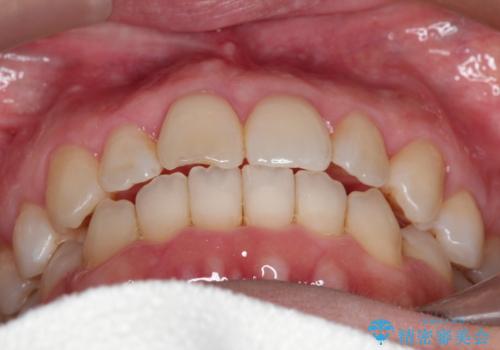

【インビザライン 】前歯のガタガタを治したい

- 前歯のガタガタを主訴に来院されました。

インビザライン で治療しました。途中は使用時間が20時間を切ることもありましたが、それでも頑張って使っていただき1年半で矯正終了することができました。